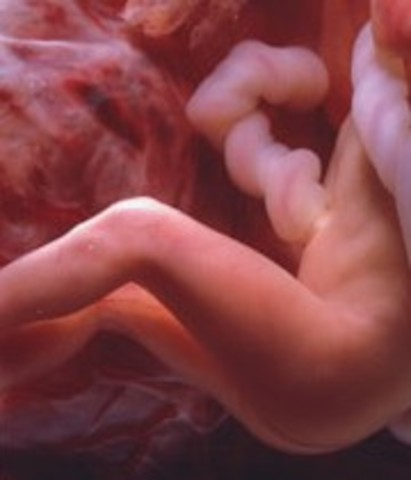

• Week 8

Week 8

The embryo now has little arms and legs in place, fingers and toes are visible. It is about 18mm and it begins to practice movement.